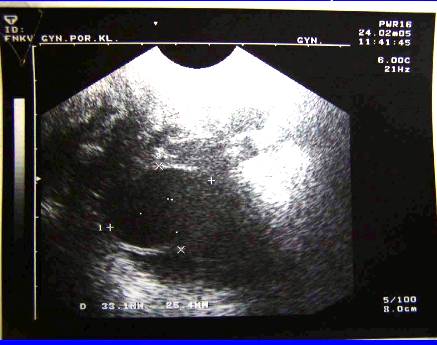

2.Recidiva (generalizace do dutiny břišní, st.p.HY a AE) pac.J.U,tu markery, punkce ascitu, cytologie

Recidiva (generalizace do dutiny břišní, st.p.HY a AE), tu markery, pac.J.U, punkce ascitu, cytologie.